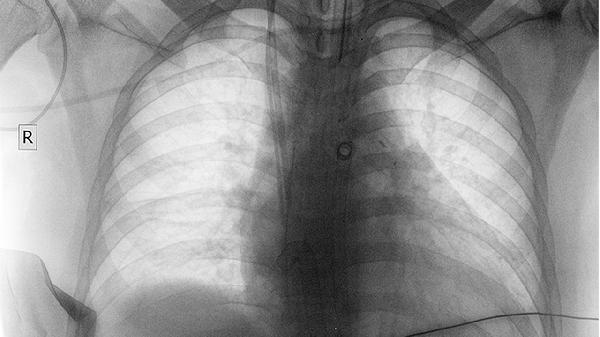

CT检查是肺癌筛查和诊断的重要手段之一,能够清晰显示肺部结节或肿块的形态、大小、位置等信息。高分辨率CT可检测到直径小至2-3毫米的肺结节,薄层CT扫描能更好评估结节边缘特征。增强CT通过对比剂显影,可观察病灶的血供情况,恶性结节多表现为不均匀强化。CT引导下穿刺活检可直接获取病变组织进行病理检查。

部分良性病变在CT上可能与肺癌表现相似,如肺结核球、炎性假瘤、错构瘤等。肺内淋巴结增生、真菌感染等也可能表现为孤立性肺结节。肺内钙化灶、脂肪密度等特征更倾向良性诊断。部分早期肺癌可能仅表现为磨玻璃样结节,需要长期随访观察变化。部分中央型肺癌可能被纵隔结构遮挡,导致CT漏诊。